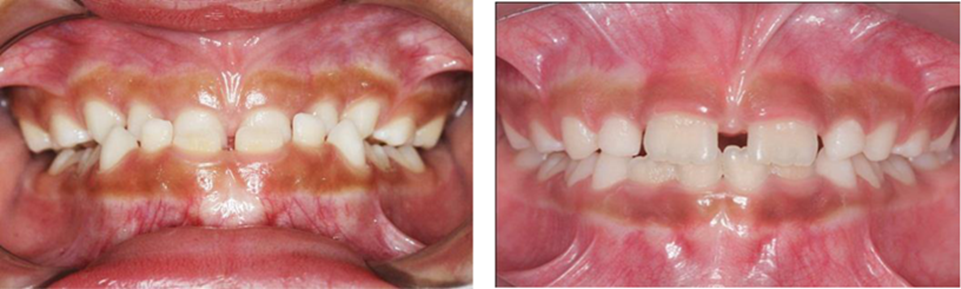

Figura 15. Fotos del antes y del después. Vista intrabucal de frente.

Autor: María Gabriela Flores Bracho. Fuente: Historia Clínica de J.I.F.A 7 años. 2012

Autor: María Gabriela Flores Bracho. Fuente: Historia Clínica de J.I.F.A 7 años. 2012. Paciente con overjet de 4 mm, overbite de -1 mm, clase 1 Molares y caninos.

Figura 17. Fotos intrabucales.